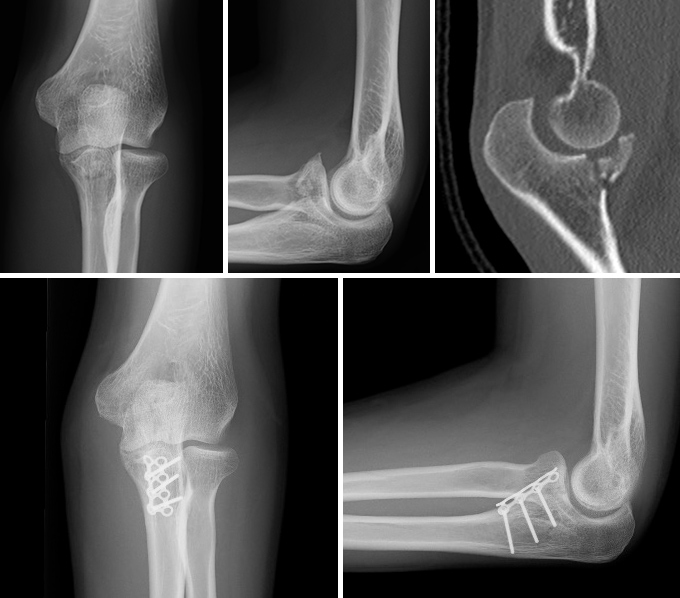

鉤状突起骨折

肘の前方を支える鉤状突起(coronoid process)が、脱臼時に上腕骨滑車と衝突して折れる外傷です。この部位は前方関節包や内側側副靱帯などの重要な支持組織が付着しており、損傷する部位により肘の安定性が大きく失われてしまいます。この部位の骨折が単独で起こることは稀であり、多くは他部位の靭帯損傷を合併しています。そのため、肘関節の外傷の全体像を把握し、総合的に判断したうえで固定を行います。不安定な骨折や脱臼骨折ではプレートやスクリューで固定を行います。肘関節全体の安定化と早期リハビリで、機能的な肘の再建を目指します。

症例 40代 男性